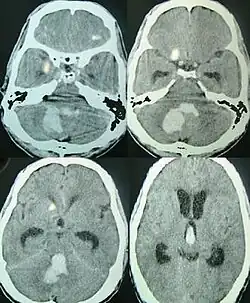

Axial CT scan showing hemorrhage in the posterior fossa[22]

Intracerebral bleeds are the second most common cause of stroke, accounting for 10% of hospital admissions for stroke.[23] High blood pressure raises the risks of spontaneous intracerebral hemorrhage by two to six times.[22] More common in adults than in children, intraparenchymal bleeds are usually due to penetrating head trauma, but can also be due to depressed skull fractures. Acceleration-deceleration trauma,[24][25][26] rupture of an aneurysm or arteriovenous malformation (AVM), and bleeding within a tumor are additional causes. Amyloid angiopathy is not an uncommon cause of intracerebral hemorrhage in patients over the age of 55. A very small proportion is due to cerebral venous sinus thrombosis.